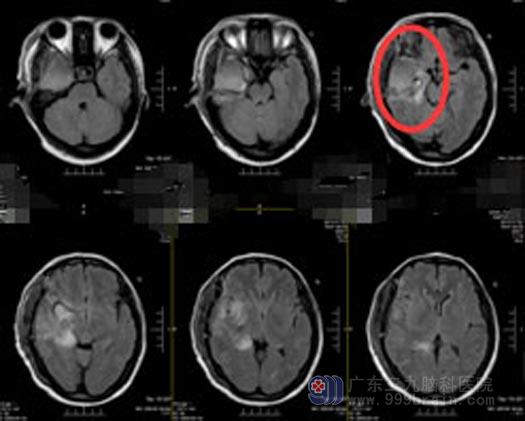

术后朱女士恢复良好,未出现脑功能区后遗症,也没有出现癫痫发作。

手术后